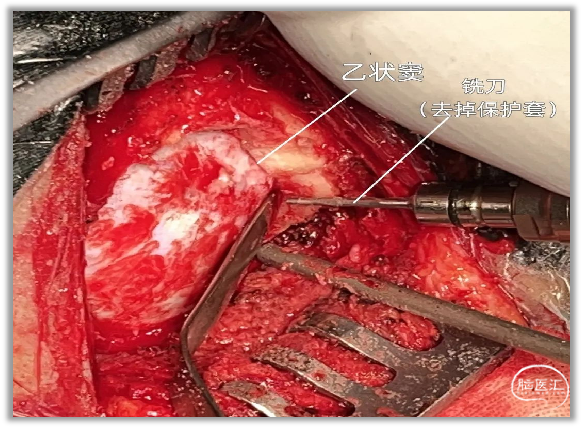

▼10.也可使用切削钻钻孔一枚,逐步磨除骨窗的骨板,显露后颅窝的硬脑膜,然后用湿明胶海绵和硬膜剥离子分离乙状窦、横窦与颅骨之间粘连。

▼11.用铣刀沿乙状窦边缘和横窦下方铣下骨瓣,上缘不必显露横窦。前缘应至乙状窦后,下缘接近颅底水平。

▼12.笔者常用铣刀(去除保护套)修整骨缘。骨窗前缘越接近乙状窦,镜下操作过程中对小脑组织的牵拉越小,可能发生的副损伤越轻微。

如果乳突气房开放,骨蜡封闭,碘伏冲洗至少两遍,术后几乎无感染。